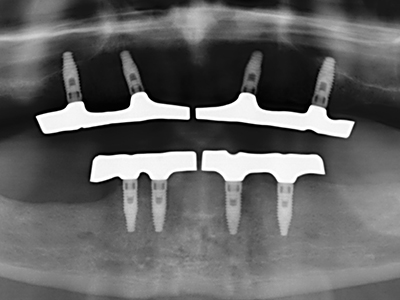

Fig. 13: En este paciente de 52 años con una anchura del hueso residual del maxilar inferior de 4 mm, hay que asegurarse de que exista refrigeración por agua adecuada durante la partición del hueso.

Fig. 14: Incorporación de cuatro implantes RSX cónicos (Bego Implant Systems, Bremen).

Fig. 15: El control radiológico realizado al cabo de un año muestra una estabilidad del nivel óseo.

Fig. 16: También condiciones intraorales estables con incorporación de los implantes en la encía queratinizada.